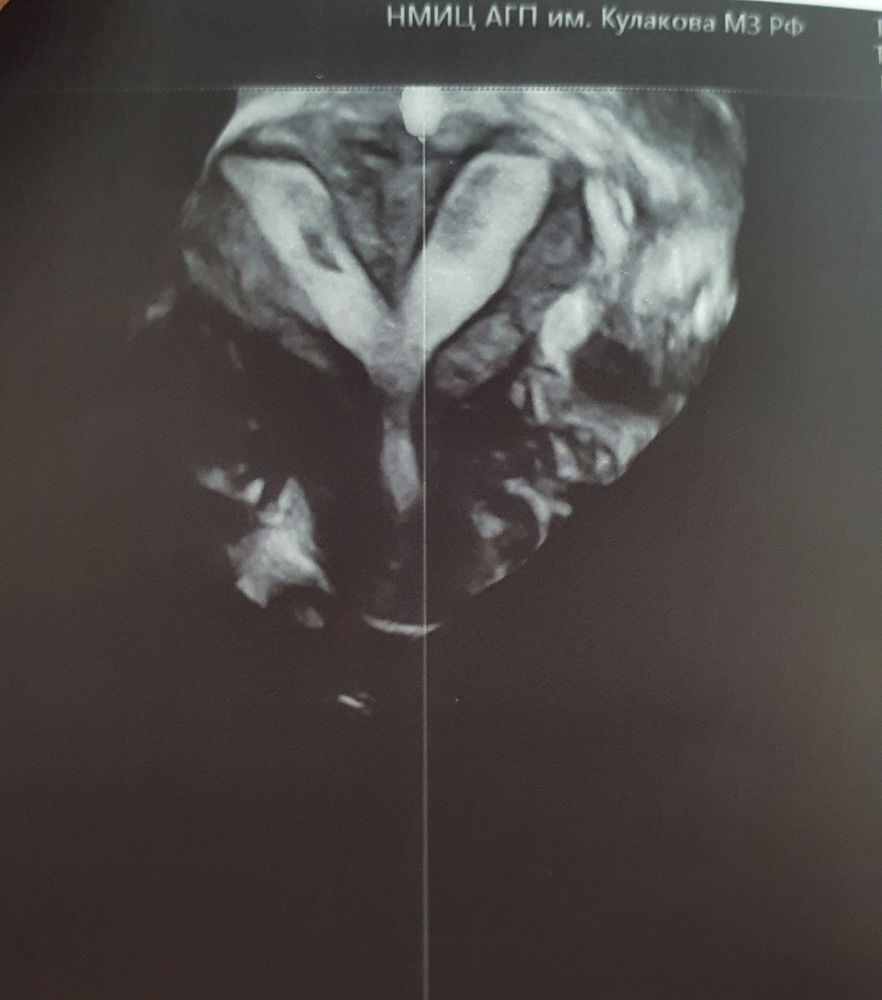

Неполная внутриматочная перегородка

Планирование и подготовка к следующей беременностиПрилетела в Москву на неделю. Вчера сходила в Кулакова на узи к Гусу А.И. и консультацию к Макияну З.Н. Оба подтвердили наличие неполной внутриматочной перегородки. Требуется операция: гистерорезектоскопия, рассечение внутриматочной перегородки, ДВ эндометрия, под лапароскопическим контролем. Думаю запланировать её на весну, чтобы было время сдать все анализы и закрыть какие-то рабочие моменты.